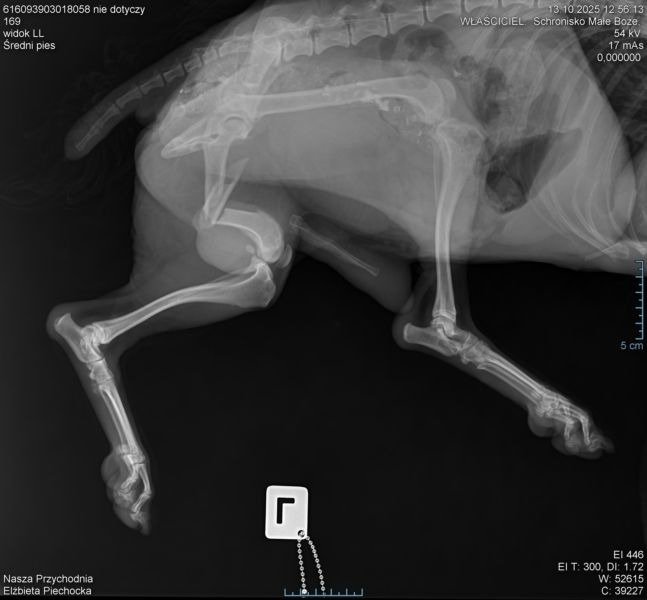

„W życiu niektórych psów cierpienie zdaje się nie mieć końca… Dziadek – bo tak nazwaliśmy tego starszego psa – trafił do schroniska w stanie, który ściska serce. Złamana w trzech miejscach łapa, ogromny ból i spojrzenie, które pytało tylko jedno: „Czy ktoś jeszcze o mnie pamięta?” Nie wiemy, co przeszedł, ale wiemy jedno – zasługuje na spokój, ciepło i życie bez bólu. Żeby mógł jeszcze kiedyś poczuć trawę pod łapami i czyjąś dłoń na grzbiecie – potrzebuje pilnej operacji. Jej koszt to 4800 zł, a czas ucieka. Dziadek jest stary, ale to nie znaczy, że bez szans. To znaczy, że musimy walczyć szybciej i mocniej. Prosimy Was – pomóżcie nam dać mu ostatnią szansę na życie bez cierpienia. Każda złotówka przybliża go do operacji, która może odmienić jego los.

Nie pozwólmy, by jego historia zakończyła się w schronisku.

Dziękujemy z całego serca wszystkim, którzy pomogą.”

Fot. Fundacja Zwierzęca Polana